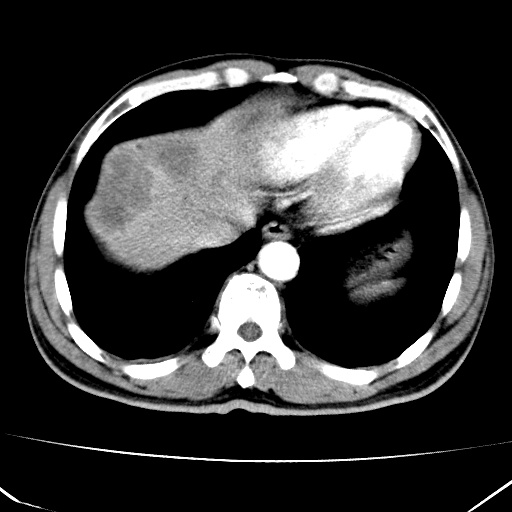

标题: CT17975:请求会诊。男、57岁。上腹部胀痛2天。临床诊断:糜 [打印本页]

标题: CT17975:请求会诊。男、57岁。上腹部胀痛2天。临床诊断:糜

肝脏多发类圆形低密度影,考虑肝脏转移瘤,肝胃韧带一淋巴结肿大,原发?胃癌?

考虑胃癌并肝脏及腹膜后淋巴结转移;不排除淋巴瘤。

肝内转移瘤,腹腔及腹膜后淋巴结转移。